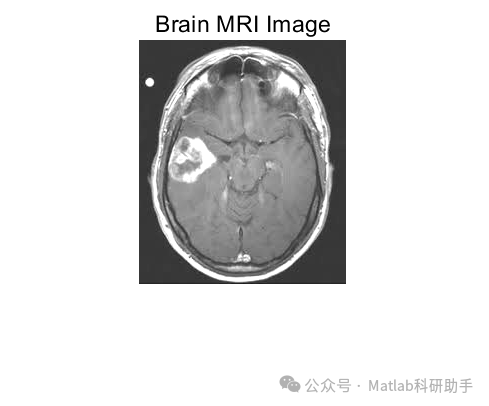

脑磁共振(MRI)图像分类是医学影像分析的重要任务,在阿尔茨海默病诊断、脑肿瘤分级等领域具有关键应用。基于主成分分析(PCA)和核支持向量机(Kernel SVM)的分类器,通过 PCA 实现特征降维与去噪,结合核 SVM 的非线性分类能力,能有效处理 MRI 图像的高维度、强噪声特性,实现精准分类。

- 脑肿瘤分级:区分低级别与高级别胶质瘤,基于肿瘤区域的纹理与增强特征,结合 PCA + 核 SVM 实现分级,辅助治疗方案制定。